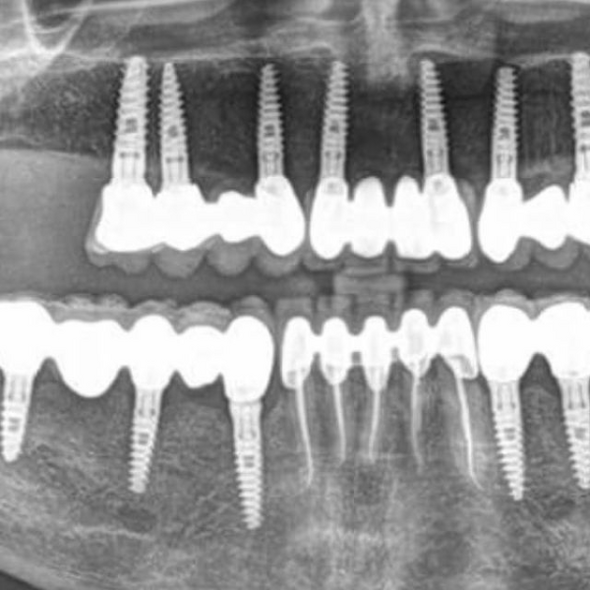

Dental Implants

Dental implants are generally inserted into the bone bases surgically under local anesthesia, with a very high success rate.

According to the need, it is possible to insert one or more implants, to replace a single tooth, several teeth (partial denture) or all the teeth of the arch (full denture).

The fixation of the implant, after it is inserted and osseointegrated into the bone base, will have the function of an artificial root, being able to support a single capsule or a bridge, or it can act as an anchor for the dental elements of an arch whole.

In general, the therapeutic process involves a healing time of 3/6 months in which osseointegration of the implant takes place in the bone before proceeding with the assembly of the crown/bridge or total prosthesis.